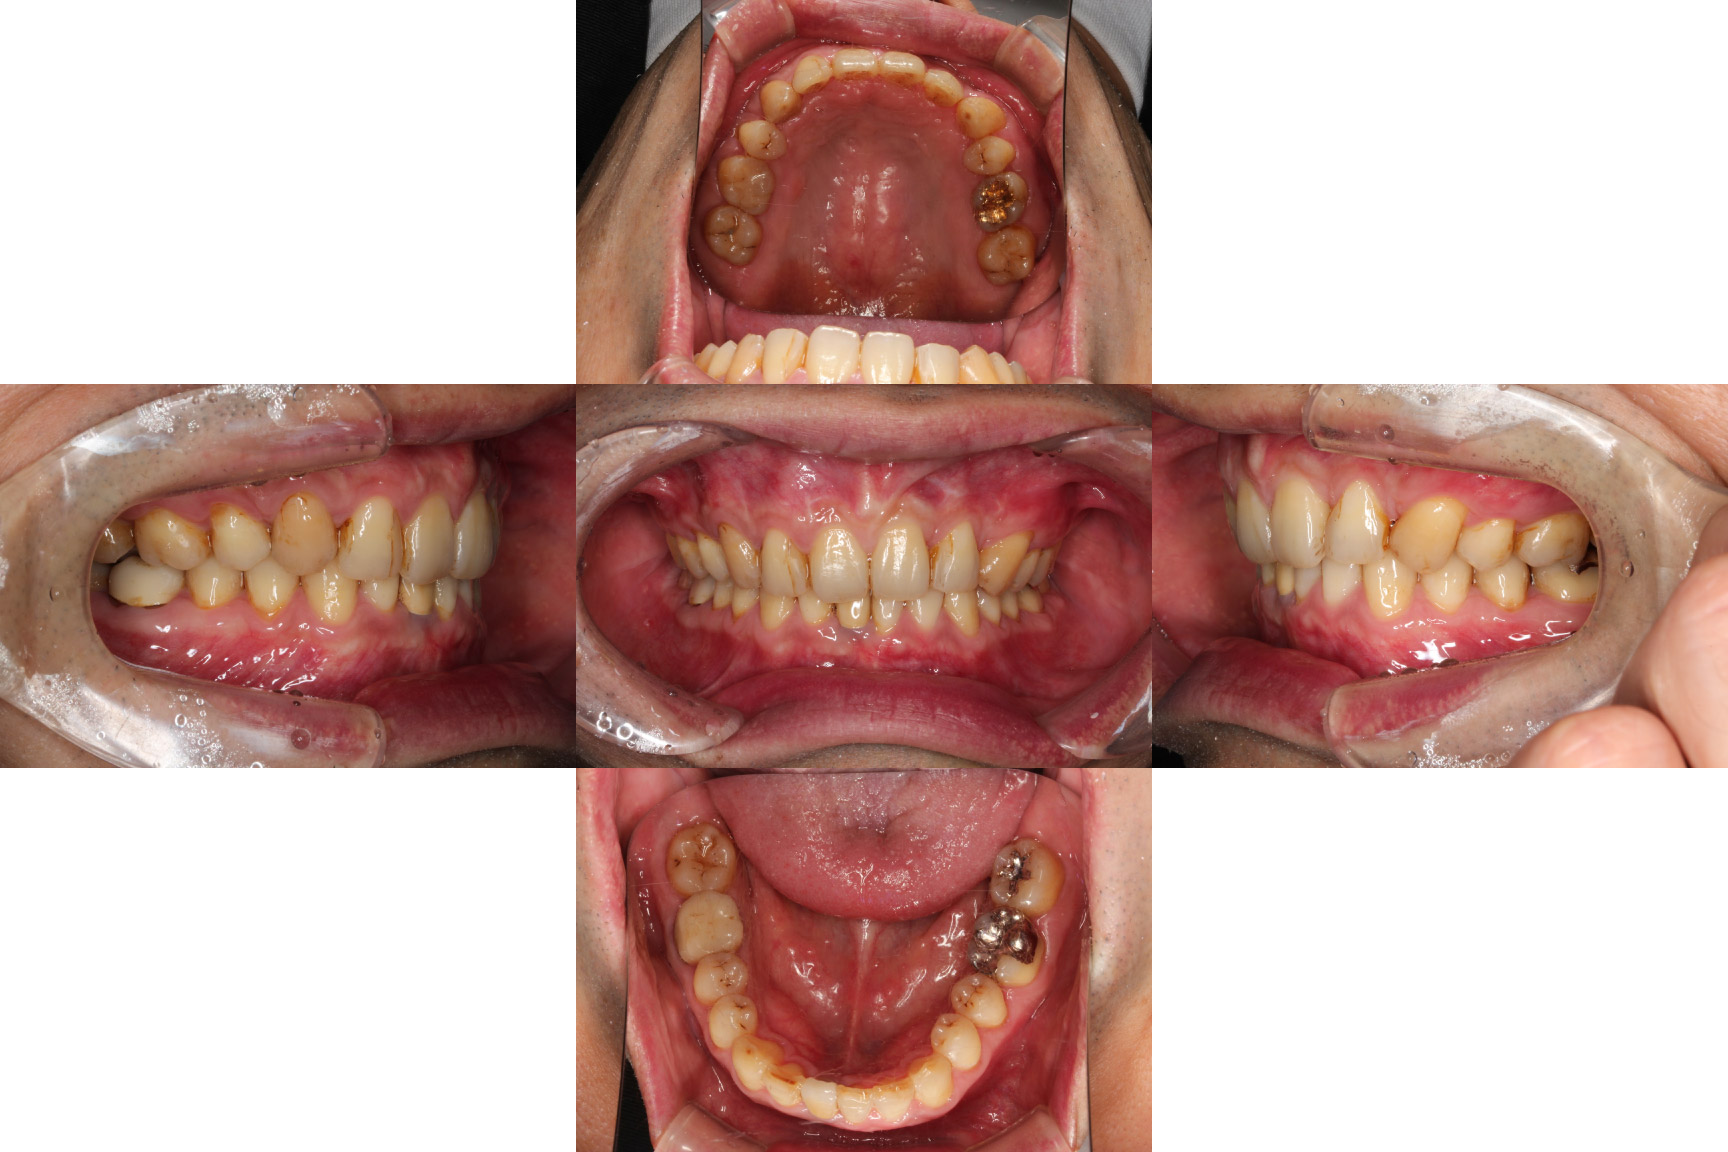

| 主訴 | 【主訴】ディープバイト,すきっ歯 【診断・症状】左上C残存、下顎右下1番欠損、上顎前突、空隙歯列、過蓋咬合 |

| 治療期間 | 約3年半(45回) |

| 抜歯 | 有(左上c、上の4,4) |

| 矯正の装置 | 裏側矯正(舌側矯正) |